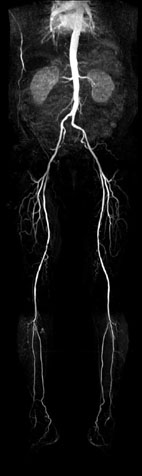

軀幹和下肢動脈血管檢查一次完成

全身磁振造影從頭、軀幹到下肢清晰的影像,對於早期體積較小的腫瘤,能為受檢者及早篩檢出來。